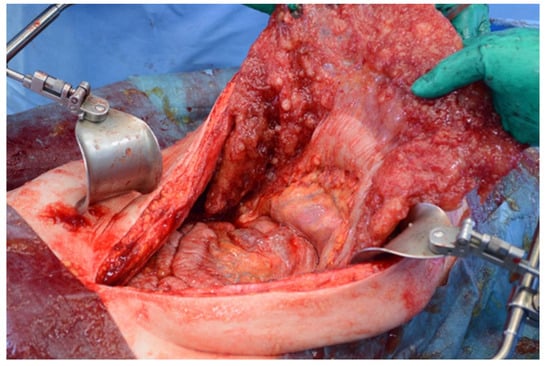

Figure 17. Intraoperative view of the abdominal cavity. The omentum contains many tumors.

Patients with a misdiagnosed rupture of the mucocele may develop pseudomyxoma peritonei. It is characterized by the presence of an abundant gelatinous substance in the abdomen. Diffuse, progressive, and abundant mucin-containing tumor cells are typical of this disease [2] (Figure 11, Figure 12, Figure 13, Figure 14, Figure 15 and Figure 16). The interval between rupture and advanced disease is several years. In our clinical series, the interval was about 5 years. In the literature, we found a wide range of this interval from 12 months to 10 years [9,10]. The natural history of PMP revolves around the “redistribution phenomenon”, whereby mucinous tumor cells accumulate in the Douglas pouch, in the diaphragm (more on the right), and the small and large omentum (Figure 17). The small intestine is less involved [4]. Pseudomyxoma peritonei is a slowly progressing disease, which fills the peritoneal cavity over time. There are several classifications of pseudomyxoma. The most commonly used is the PSOGI classification [2]. Mucinous accumulation progresses to malnutrition, bowel obstruction, and respiratory compromise. Rarely, the tumor may spread to the pleural cavity. This has been described in 5.4% of cases. It may occur spontaneously or as a result of diaphragmatic injury during cytoreduction [8,11].

Figure 11, Figure 12, Figure 13, Figure 14 and Figure 15. Advanced stage of the disease. The abdomen is full of tumors and mucin. Typical signs are heterogeneous or hypodense masses in the form of lobules often with septa, which could be enhanced by contrast and could be associated with calcifications.